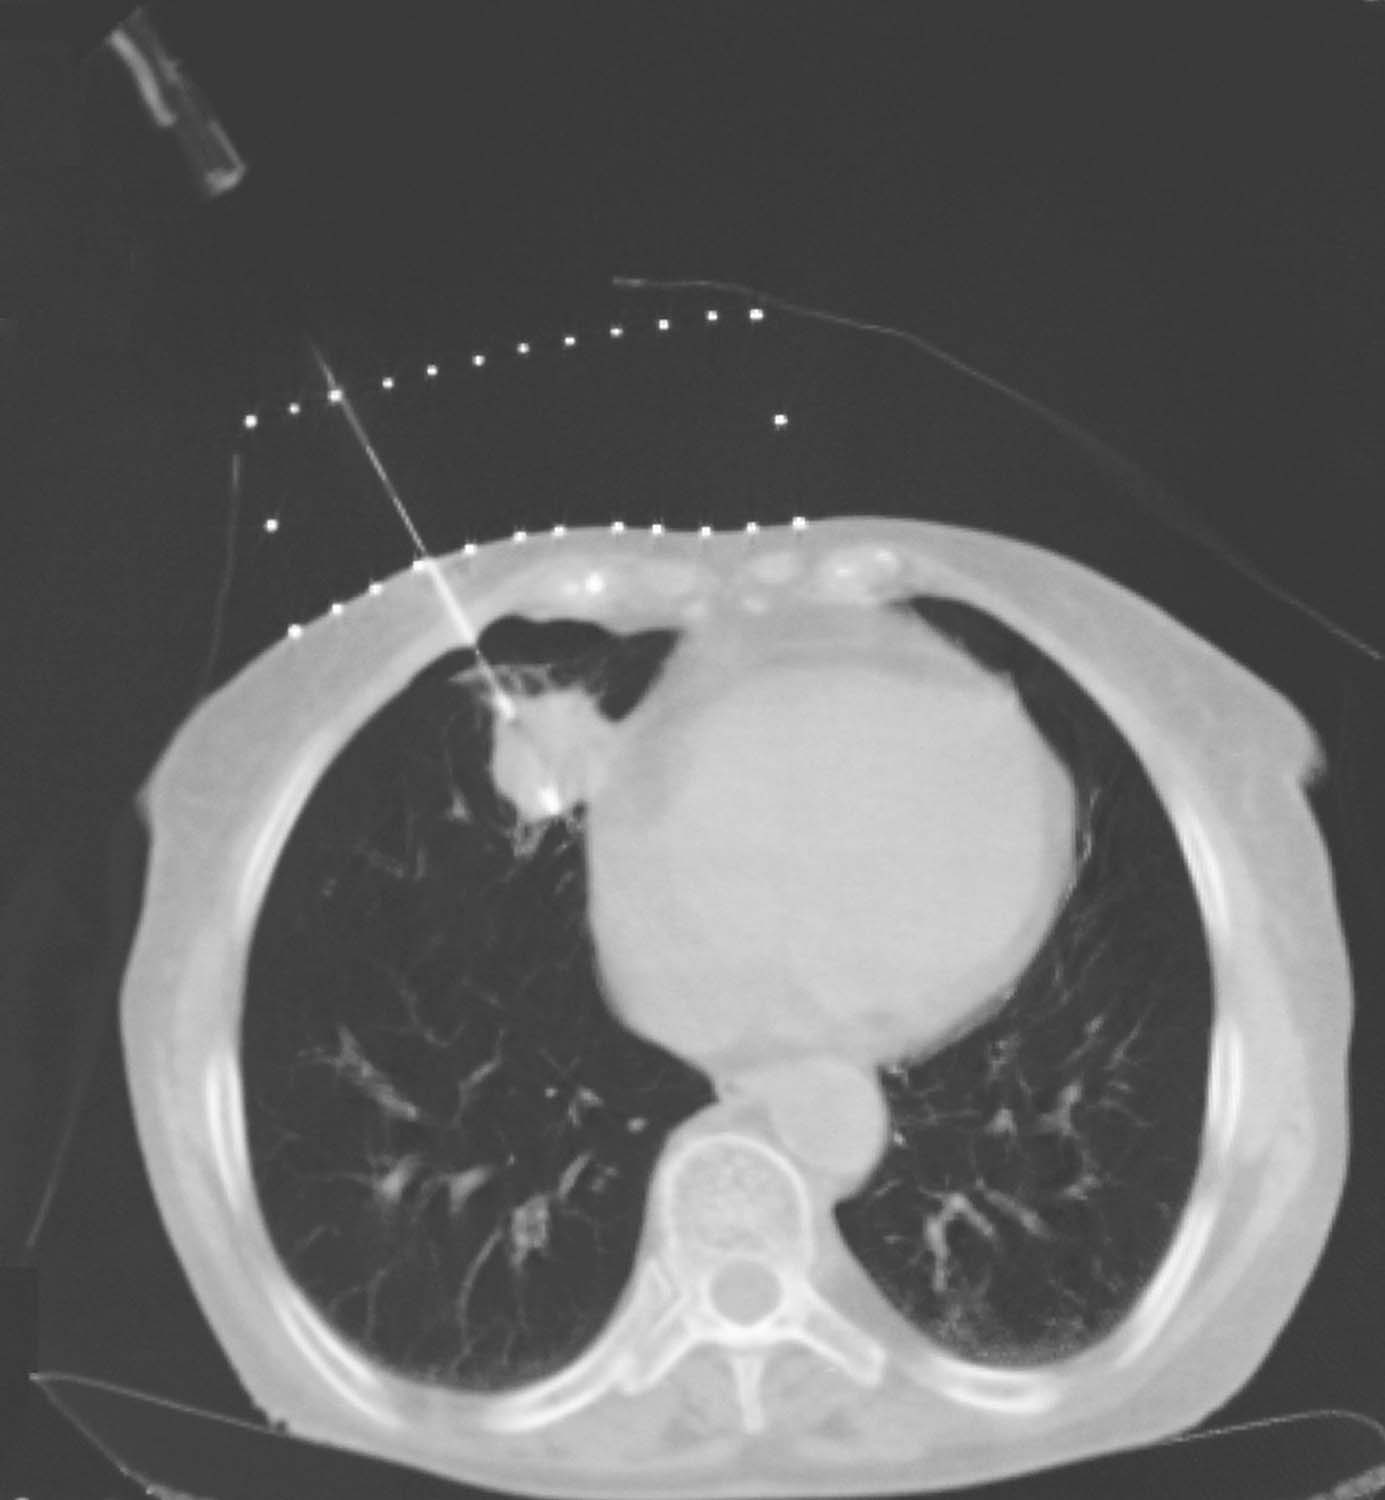

患者取与术前CT扫描相同体位,真空负压垫固定体位,防止穿刺过程中因体位变动给穿刺带来的不利影响。将导航支架与CT碳纤维床板相连接,以0.5cm层厚扫描,选取病灶中心层面,将一个预定进针点在皮肤表面做出大十字标记,消毒、铺巾、局麻,安装模板,用激光灯校准模板,使激光灯的 x 轴和 y 轴投影与模板表面的标记线相重合,利用数字化角度仪或者水平仪调整模板的角度和方向,使模板在 y 轴方向的角度为零,调整 x 轴方向的角度,与术前计划保持一致。选择病灶中心层面,参考术前计划,将数根穿刺针抵达皮肤表面,扫描观察针尾走行方向,再次校准模板,然后测量进针的深度,完成该层面的进针,如果是肺等移动度较大的脏器,可以先插入2~3根固定针,将病灶与模板迅速“绑定”(图4-3-1),然后再依次完成其他层面的进针,如果遇到坚韧骨骼遮挡,使用捻针或骨钻打孔技术破骨插植,待完成所有层面的进针以后再植入粒子。

图4-3-1 进针过程

例1 患者男性,72岁,左肺鳞癌侵犯胸壁并同侧肺门淋巴结转移,T4N1M0。2018年1月16日行共面模板引导放射性粒子植入术(图4-3-2~图4-3-7)。